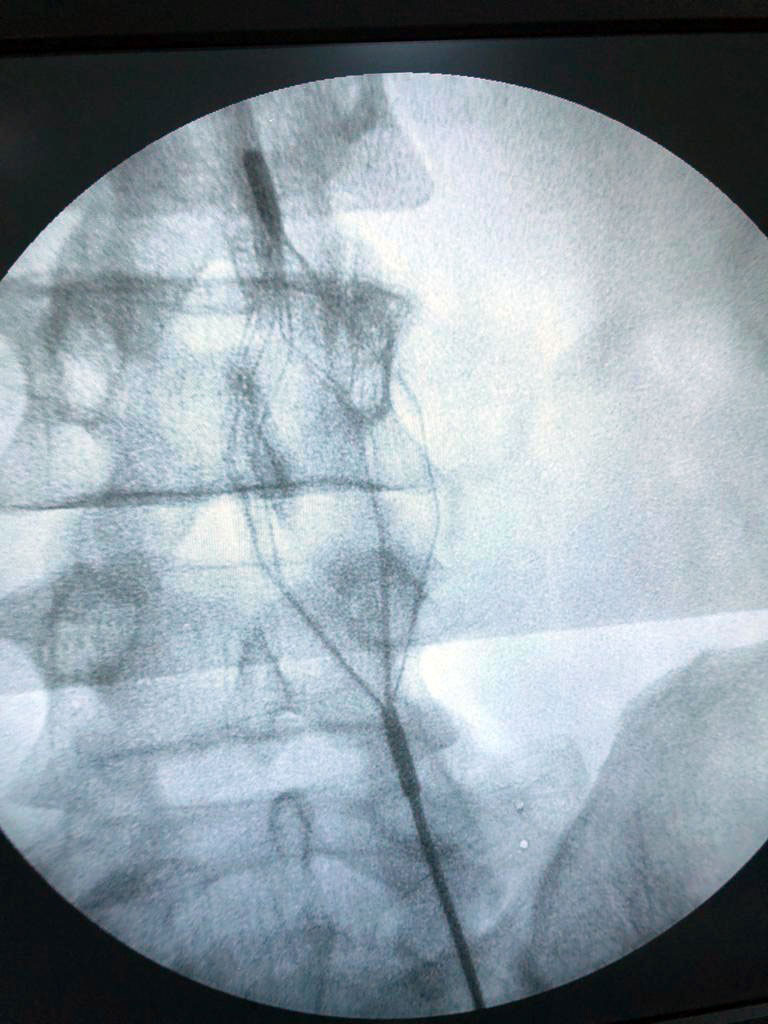

Hastanın yıllarca kullanmış olduğu ilaçlara rağmen sağlığına kavuşamamasına karşılık Türkiye'nin geliştirdiği 4 milli tıbbi cihaz ile birlikte ( TPS, Mantis, Dovi ve Viper ) sadece 2 saat süren bir cerrahi müdahale ile artık hasta ayağa kalkabiliyor.

En son Bingöl Devlet Hastanesi’nden Op. Dr. Oktay Tüydeş ve Op. Dr. Abdurahman Muratoğlu tarafından, sol bacağında Trombüs ( kanın bir atardamar ya da toplardamar içinde ya da bir organda pıhtılaşması ) saptanan hastanın ameliyatı gerçekleştirildi.

Gerçekleştirilen ameliyatta, hastanın vücudundan yaklaşık 350 cc, yani yarım kilogram pıhtı çıkartıldı ve hasta 2 gün içerisinde iyileşerek taburcu edildi. Riskli grupta yer alan bu ameliyatlar yalnızca Bingöl Devlet Hastanesi’nde değil artık Türkiye’nin 81 ilinde uygulanacak.